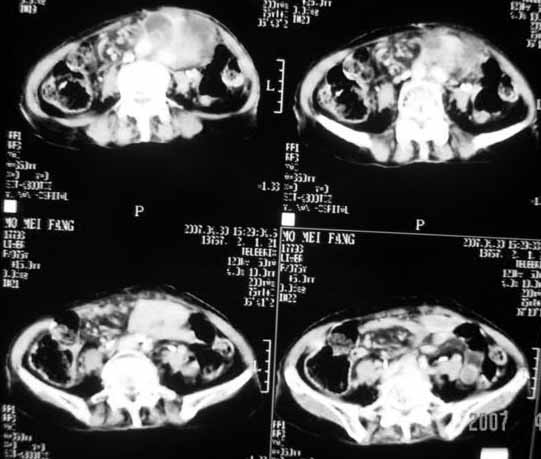

以下是引用天南地北在2007-4-30 17:42:00的发言:[br]增强扫描显示腹主动脉给包绕、推移。肿块不规则强化,[br]修正我在平扫的诊断[br]支持考虑:间叶源性肿瘤可能性大

以下是引用余辉在2007-4-30 18:01:00的发言:[br]病灶前方的条状增强影是什么?若是胰腺,位置似乎有点低,若是十二指肠,似乎又不诫该是那样强化,姑且将其看作胰腺吧,那么考虑来源于胰腺粘液囊腺瘤可能性大,其次考虑来源于肠系膜或者后腹膜的肿瘤如平滑肌肉瘤,异位嗜铬细胞瘤及淋巴瘤等。

以下是引用zyx168在2007-4-30 23:24:00的发言:[br]考虑:间叶源性肿瘤可能性大